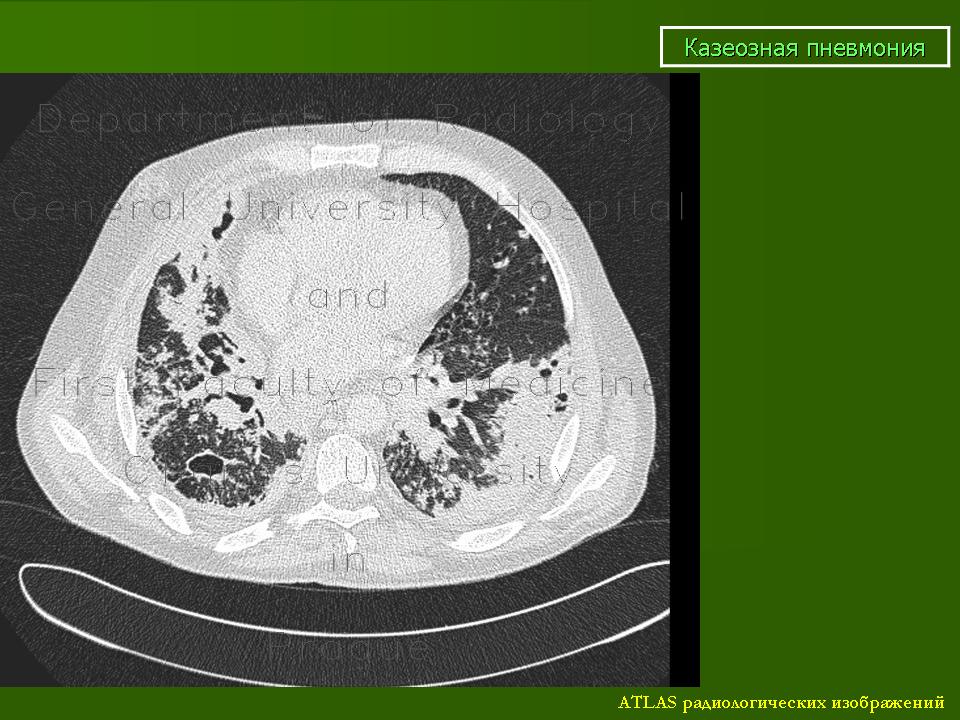

Казеозная пневмония.

КП - одна из самых тяжелых форм ТБ, часто как осложнение ряда других форм; характерен выраженный казеозно-некротический компонент воспаление, быстрое прогрессирование, множественные полости распада, высокая летальность;

Патоморфологически: массовая гибель клеточных элементов и постепенное распространение казеозного некроза (ацинозная - ацинозно-лобулярная - сливная лобулярная - сегментарная КП и т.д.); вследствие гибели клеток ИС и выброса протеолитических ферментов происходит расплавление очагов казеоза с формирование полостей (множественных острых каверн); возможно лимфогематогенное распространение процесса

1. лобарная пневмония: затемнение всей или большей части доли, вначале однородное, затем с участками просветления бухтообразной формы с нечеткими контурами; в дальнейшем видны каверны

2. лобулярная пневмония: крупные очаговые тени и небольшие фокусы (до 1,5 см) неправильной формы, средней или высокой интенсивности, с нечеткими контурами; часто располагаются симметрично

Небольшой пример.

По клинике (острое начало, интоксикация, кровохарканье), рентген-исследованию, и мокрота (Mbt+). К сожалению, информации мало, сам пациента не наблюдал, снимки архивные, 2009 года. Вот все, что смог выжать у очевидцев, то и передал.